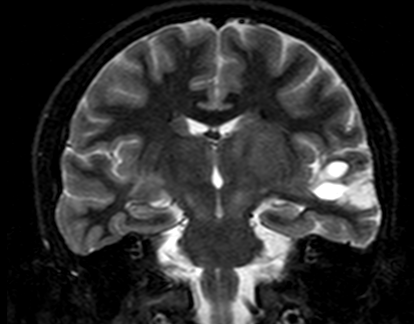

Neurofibroma bright objects

with cystic changes noted on MRI

(T2 weighted imaging) in a patient

with refractory epilepsy